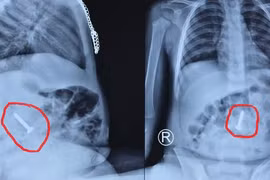

Việc đào tạo, chuyển giao thành công kỹ thuật “lấy, ghép thận từ người sống và người cho chết não” từ Bệnh viện Hữu nghị Việt Đức cho Bệnh viện Hữu nghị Đa khoa Nghệ An đã tạo ra bước ngoặt lớn về phát triển chuyên môn kỹ thuật trong y tế nói chung cũng như trong lĩnh vực ghép tạng nói riêng… Nhờ đó, không chỉ người dân Nghệ An mà người bệnh trong khu vực và cả các bệnh nhân nước bạn Lào cũng được hưởng lợi.